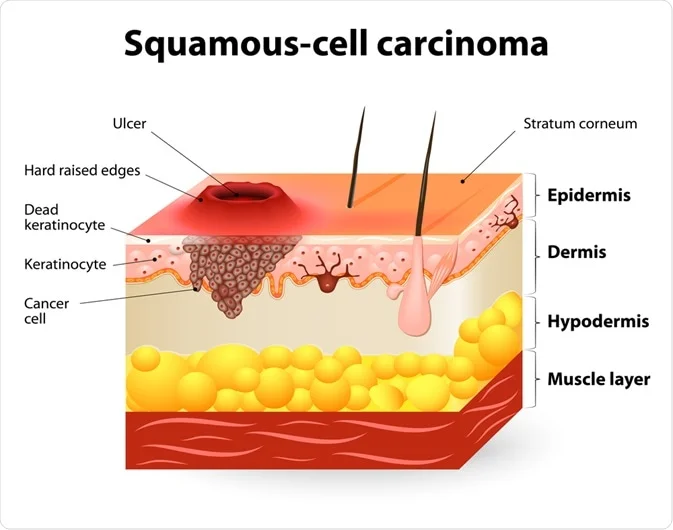

Squamous Cell Cancer

Squamous cell carcinoma of the skin is a common form of skin cancer that develops in the squamous cells that make up the middle and out...